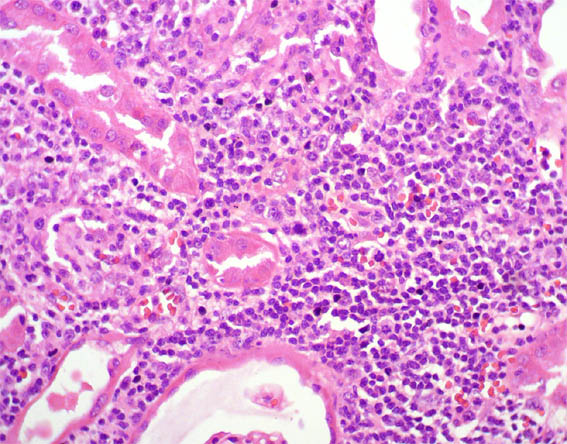

Figure 4. H&E, X400.